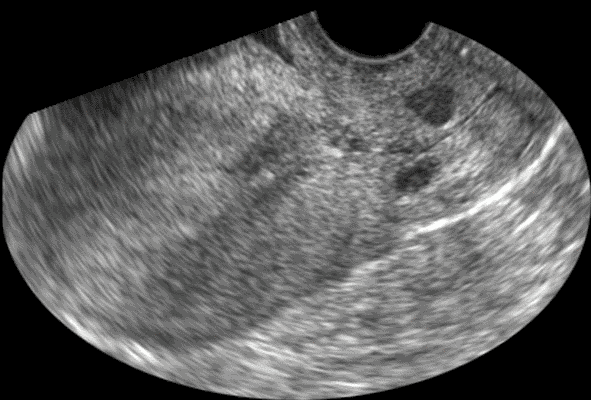

- Le kyste

glandulaire du col utérin et le kyste de Naboth :

- Connu

aussi sous le nom de follicule de Naboth, de kyste glandulaire ou de kyste de rétention ; il se forme sous la surface épithélial

du col utérin lorsque l'orifice d'une crypte glandulaire endocervicale

est obstrué par l'épithélium cylindrique métaplasique,

l'épithélium glandulaire cylindrique reste actif à

l'intérieur de la crypte obstruée et il sécrète

du mucus qui dilate la glande et lui donne l'aspect kystique (ou folliculaire)

de taille variable

Ces kystes glandulaires rétentionnels sont visibles sur l'exocol,

mais parfois ils sont situés profondément dans le col (comme c'est le cas sur cette image), près du canal endocervical

et invisibles à l'observation du col par le spéculum

ou le colposcope.